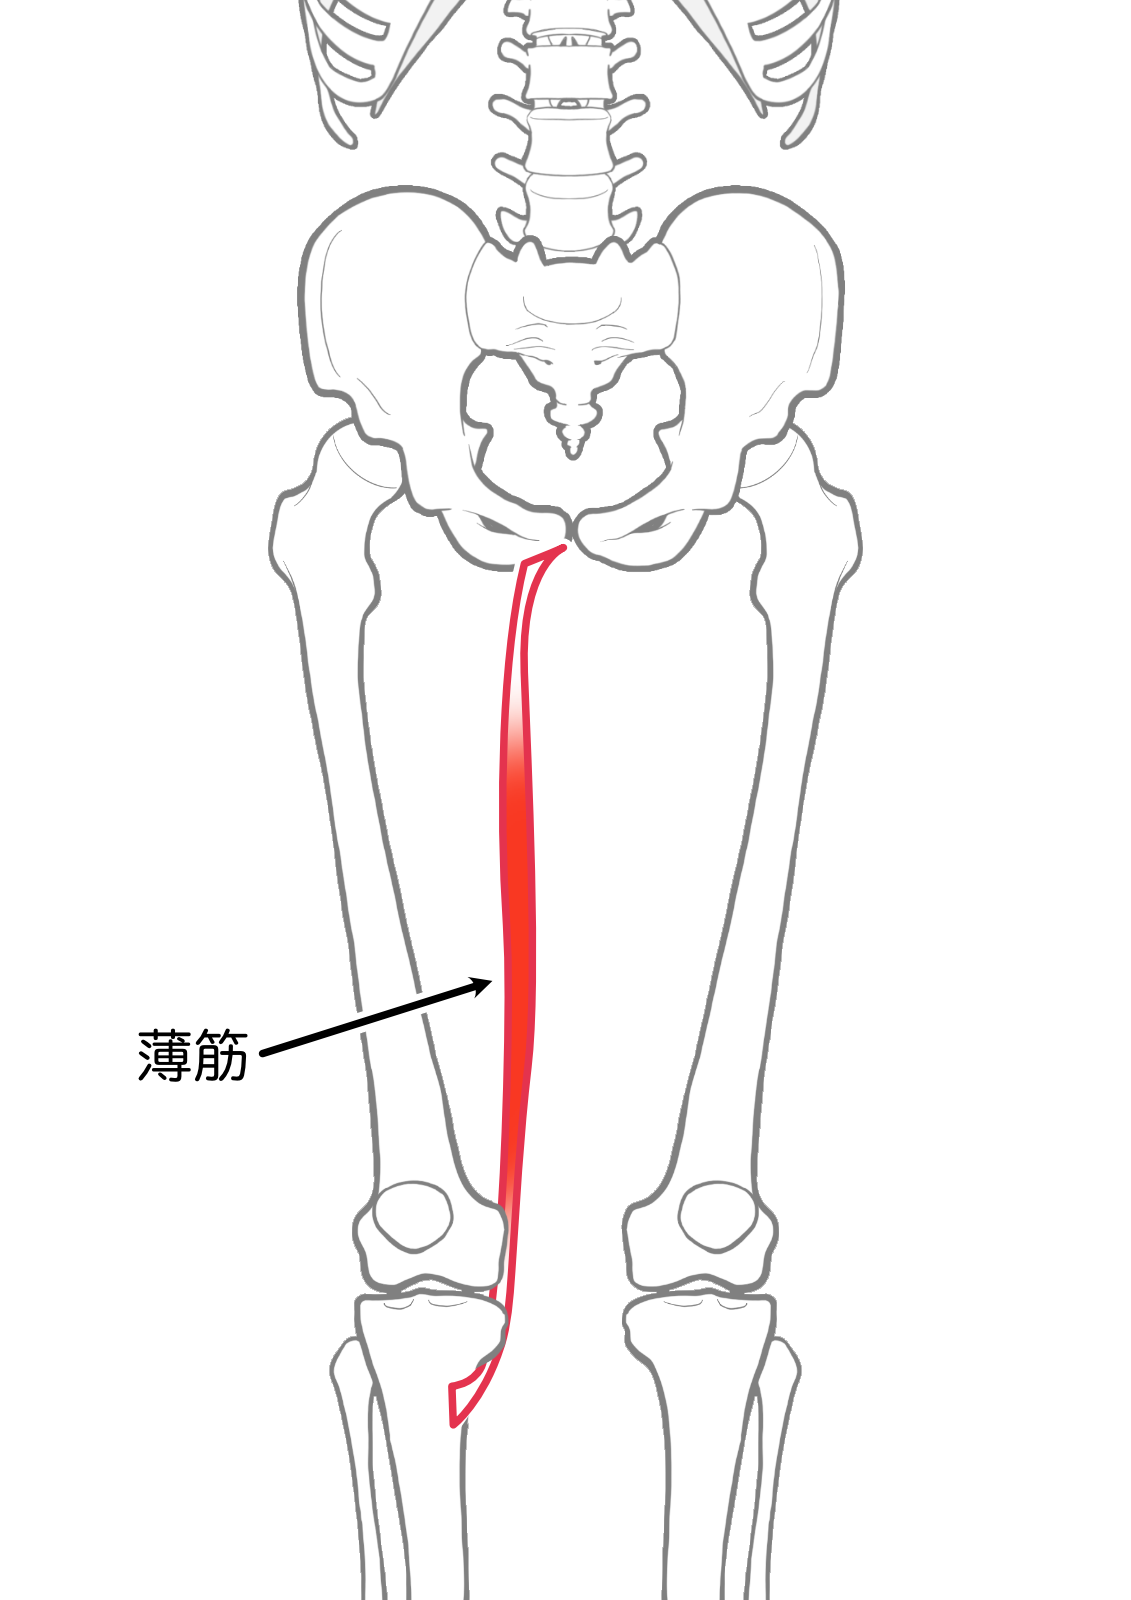

薄筋

| 起始 | 恥骨体,恥骨下枝 |

| 停止 | 脛骨上部内側面(鵞足) |

| 神経 | 閉鎖神経L2-4 |

| 作用 | 膝関節屈曲,内旋 |

- 薄筋

- 薄筋